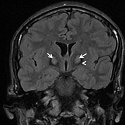

Maladie dÂ’Hallervorden-Spatz chez un adulte jeune

Badreeddine Alami, Siham Tizniti

PAMJ. 2014; 19: 62. Published 23 September 2014